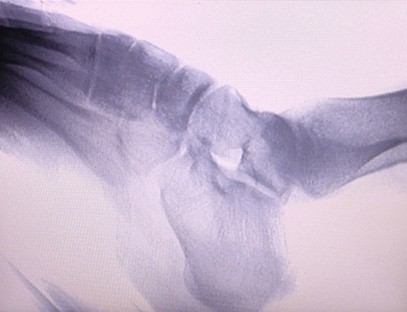

دستگاه اشعه ایکس ارتوپدی ما یک محصول با کیفیت بالا است که به ویژه برای تصویربرداری ارتوپدی طراحی شده است. می توان از آن برای تشخیص و برنامه ریزی درمان بیماری های مختلف ارتوپدی، از جمله شکستگی، دررفتگی، آرتریت و تومورهای استخوانی استفاده کرد. این دستگاه مجهز به فناوری پیشرفته اشعه ایکس است که تصاویر با کیفیت بالا را با کاهش قرار گرفتن در معرض تابش امکان پذیر می کند. این دستگاه دارای سیستم تصویربرداری با وضوح بالا است و می تواند تصاویری از هر ساختار استخوانی را با وضوح بسیار بالا ثبت کند.

1. تشخیص شکستگی ها، دررفتگی ها و سایر آسیب های استخوانی.

2. ارزیابی بیماری های مفصلی مانند آرتریت، بیماری دژنراتیو مفصل و پوکی استخوان.

3. تشخیص تومورهای استخوانی و سایر رشدهای غیر طبیعی.